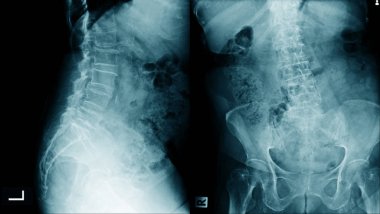

Sırt ve kereste omurgasının röntgen ışınları spondilotik değişimleri, sırt ve kereste dikenlerinin düzleştirilmesini, omurgalar arası disk alanlarının bozulmamış olduğunu, sırt ve kereste dikenlerinin Spondylosis 'inin bozulmamış olduğunu gösterir.